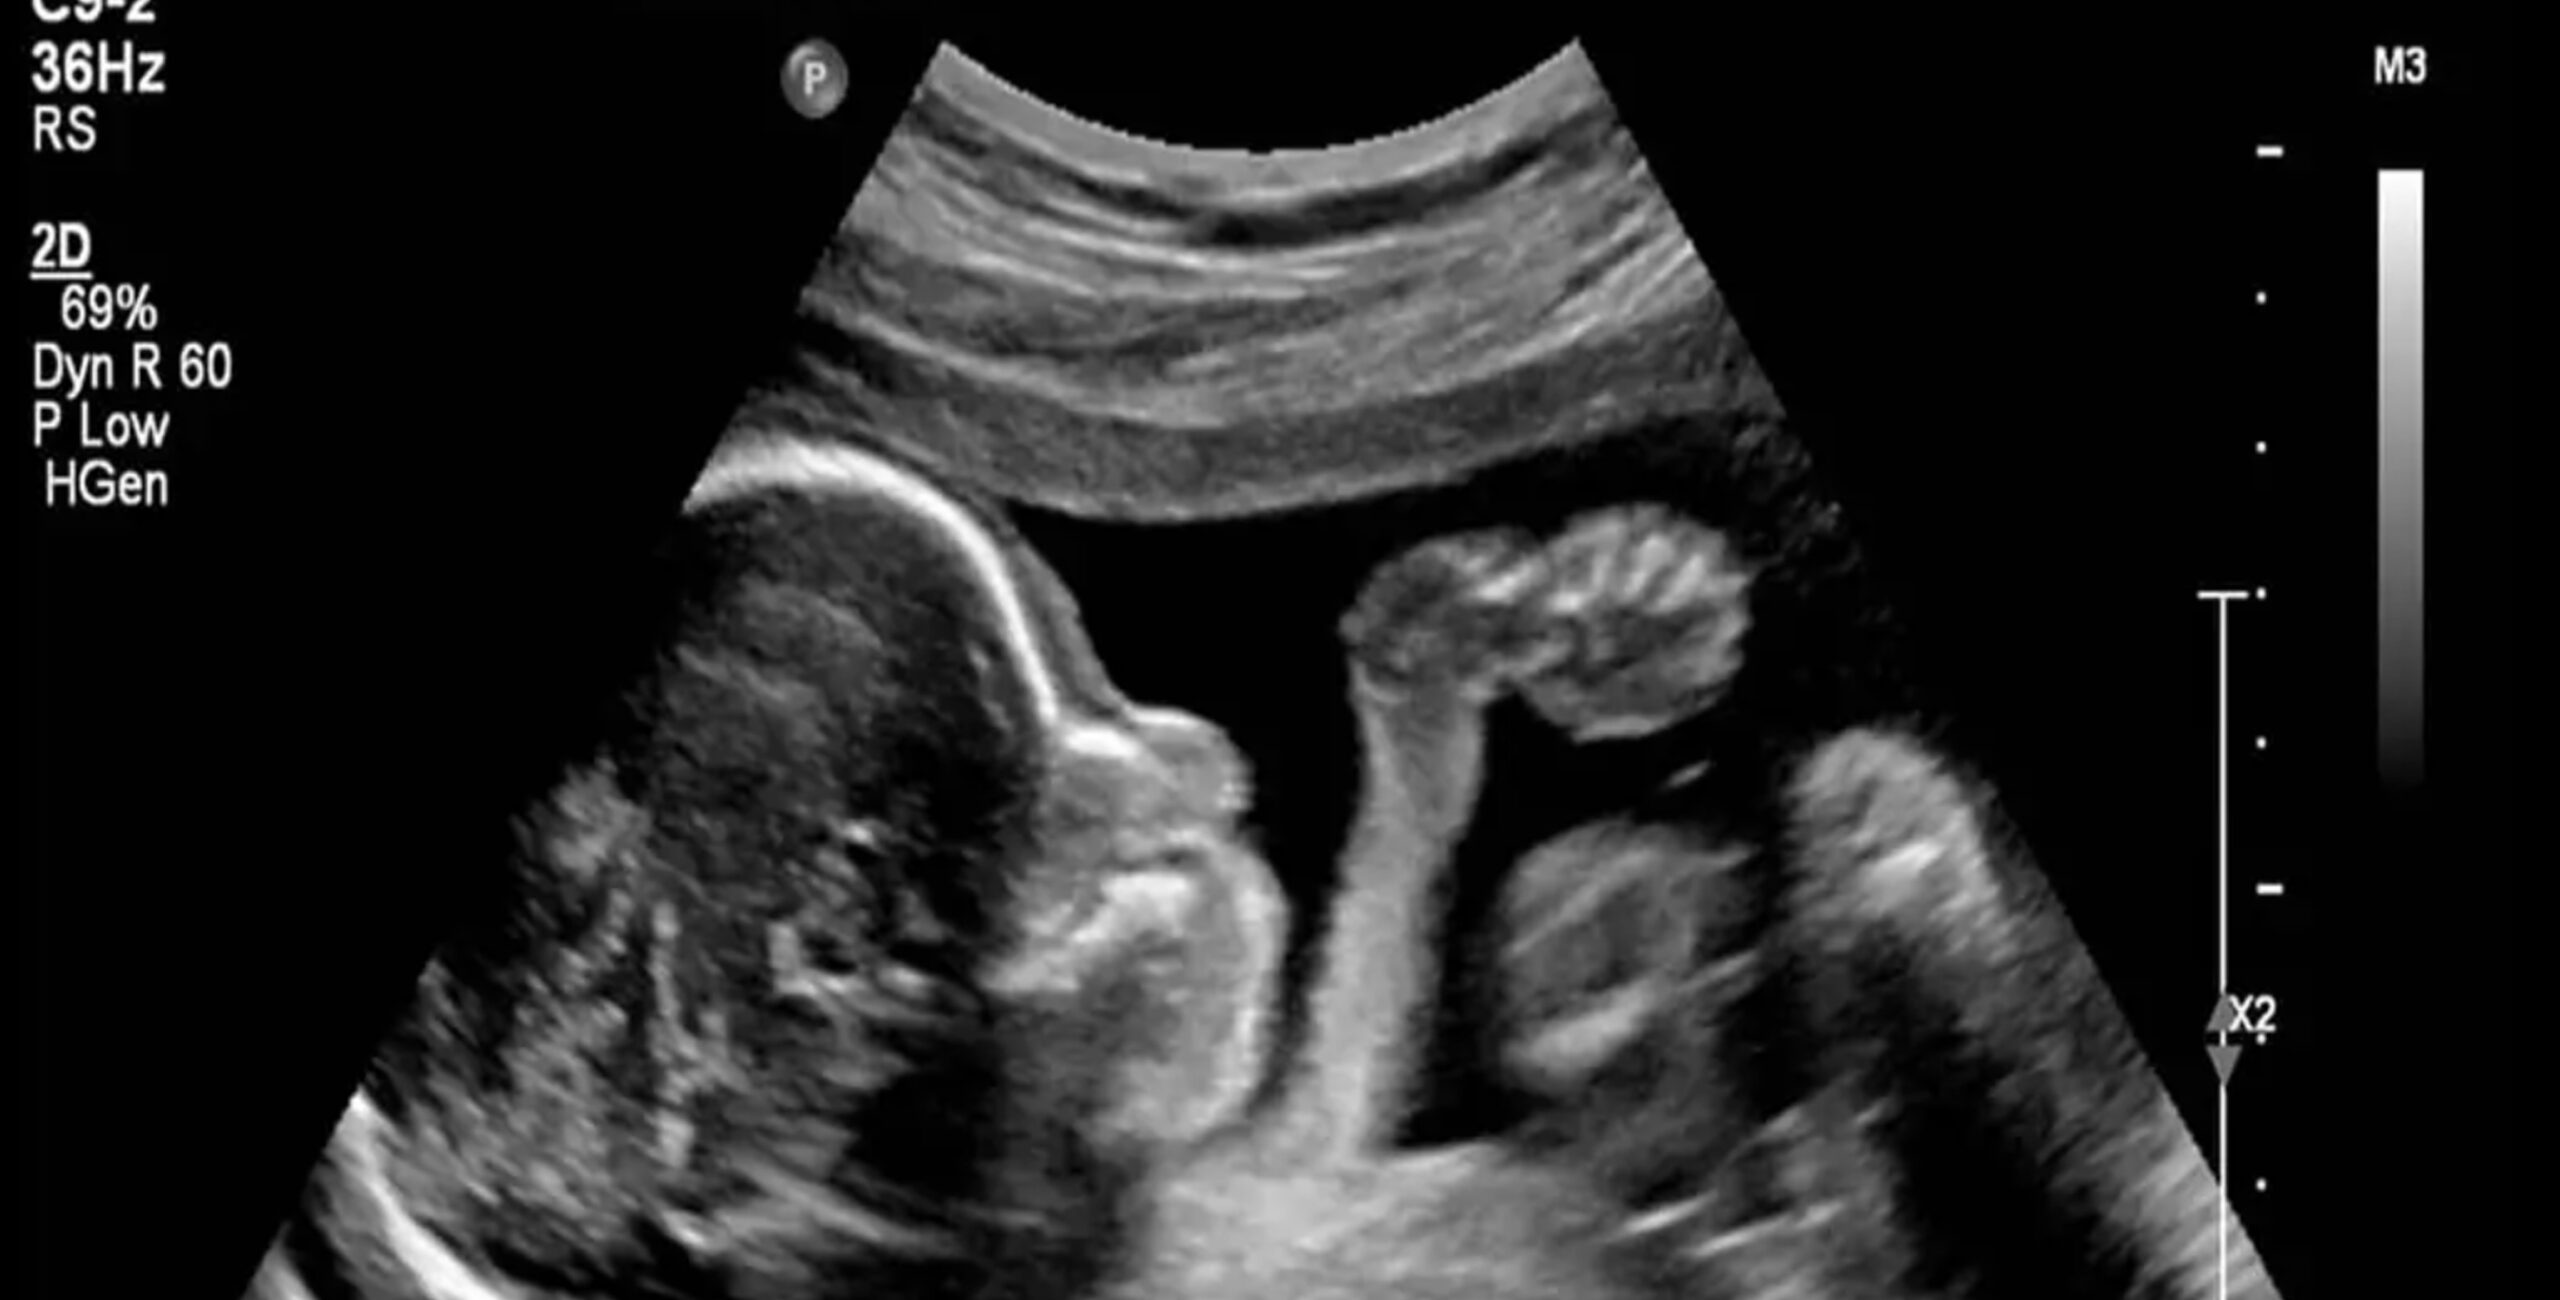

حالا اگر بدانیم بیماریای در میان ما شایع شده که هر سال جان ۳۰۰ هزار هموطن ما را میگیرد چه احساسی پیدا میکنیم؟! یا از آن بدتر، اگر بدانیم این یک بیماری نیست، این یک ابرقاتل سریالی است که سایه شومش را همینجا در همسایگی من و شما پهن کرده چه؟! یک روح شیطانی که شاید یک روز در جسم ما هم حلول کند! کودککش همان کلیدواژهای است که ما برای جانیترین انساننماهای روی زمین از آن استفاده میکنیم. اما وقتی پای بهانههای بزکشده برای ما انسانها وسط میآید، دیگر کشتن یک جنین، قتل به حساب نمیآید!

«بدن من، انتخاب من» شعاری است که فمنیستها تلاش کردند از آن در جهت عادیسازی سقط جنین استفاده کنند. شعاری که بیش از هرچیز پایه غیرتوحیدی و شرکآلودهی آن توی ذوق میزند. آنها میگویند تفاوت میان کشتن جنین و کشتن یک بچهی سه ساله، در «تجربهی زندگی» است! یعنی آن بچه چون زندگی در این جهان را تجربه کرده پس حق ادامهی آن را دارد اما جنین در رحم را به دلیل نداشتن این تجربه میشود از ادامهی زندگی محروم کرد! به همین سادگی. چون هیچکدام از ما احساسی که در زمان جنینی در رحم مادرمان تجربه میکردیم را بهخاطر نداریم پس لابد جنین اصلا حسی به زندگی ندارد! ما استادانه ملاکهای اخلاقی زندگیکردن را فرسنگها جابجا میکنیم. مثلا در نگاهمان سپردن فرزند به بهزیستی شاید از قتل او هم بدتر باشد! بهزیستی واژهی منفوری است وقتی دربارهی فرزندانمان به آن فکر میکنیم اما سقط جنین میتواند هزاران بهانهی بزکشده داشته باشد. اما وقتی کمی از رسانه فاصله بگیریم و منطقی فکر کنیم خیلی زود میفهمیم شعار «نمیخواهم فرزندی را به این جهان پر از سیاهی و نفرت بیاورم.» به این معنی است که: پس او را میکشم تا سهمی در سیاهترکردن این جهان داشتهباشم!